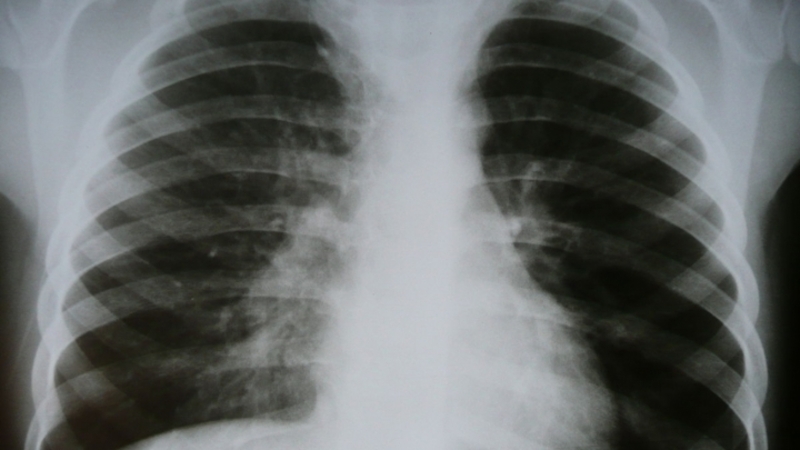

Ставропольчанка с туберкулёзом принудительно отправится в диспансер

В Андроповском районе по решению суда женщину с туберкулёзом принудительно отправили в краевой диспансер, передаёт пресс-служба ставропольской прокуратуры.

Нарушение было выявлено в ходе проверки исполнения законодательства о предупреждении распространения опасного заболевания в районе. Оказалось, что в противотуберкулёзном кабинете Андроповской центральной больницы на учёте состоит женщина из Курсавки. Ей поставлен диагноз «туберкулёз лёгких», однако пациентка не посещает кабинет и не хочет лечиться.